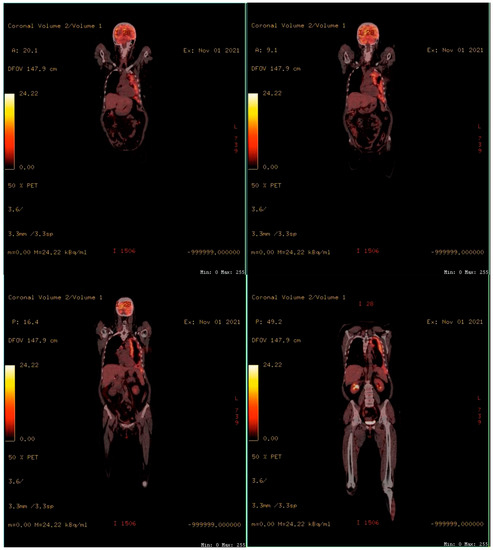

In 2019, the patient was admitted to a local hospital in the respiratory department for dyspnea on exertion during moderate physical activity. A clinical evaluation and thoracic computed tomography (CT) revealed the presence of pleural effusion in the left hemithorax (Figure 1a). The result of the biochemical and cytological analysis of the pleural fluid showed a lymphocyte-predominant exudate. The patient was diagnosed with pleurisy of an unspecified etiology, and antibiotic and anti-inflammatory treatment was recommended for 7 days. The evolution was favorable, and the pleural fluid was reabsorbed.

In September 2021, the patient was admitted to a thoracic surgery department. A thoracic CT showed pleural effusion (Figure 1b). Thoracentesis and a pleural biopsy were performed, and the patient was diagnosed with “Diffuse malignant mesothelioma with epithelioid elements”.

In January 2022, the patient’s condition worsened, and the patient reported dyspnea at rest and orthopnea. A thoracic CT showed right pleural effusion (Figure 1c). Thoracocentesis was performed, and the analysis of the pleural fluid revealed the presence of lymphocytes and mesothelial cells. The cultures for mycobacterium tuberculosis were negative. Following antibiotic and anti-inflammatory treatments, a slight improvement in dyspnea was noticed.

Figure 1. Thoracic computed tomography: (a) Thoracic CT performed in 2019 showing pleural effusion in the left hemithorax; (b) Thoracic CT performed in 2021 showing pleural effusion in the left hemithorax; (c) Thoracic CT performed in 2022 showing right pleural effusion.